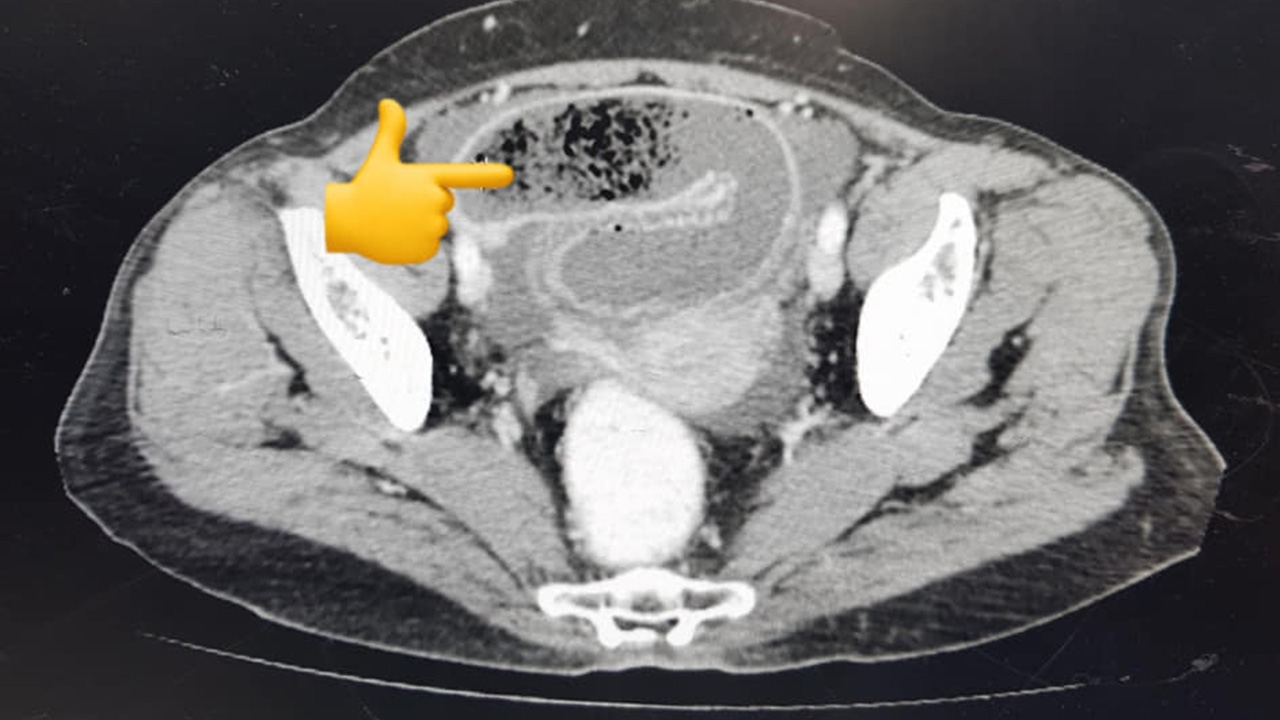

เมื่อ CT Scan ก็พบก้อนแปลกๆ อุดลำไส้เล็ก หลังจากเปิดไส้แล้วหยิบก้อนออกมา พบว่าเป็นก้อนอะไรไม่รู้ ขนาดไข่ไก่ ก้อนค่อนข้างแข็ง แต่ยังบี้ได้ เมื่อบี้แล้วกลายเป็นเศษเส้นฝอยๆ เหมือนหนังยาง นิ่มๆ ไม่ใช่นิ่ว